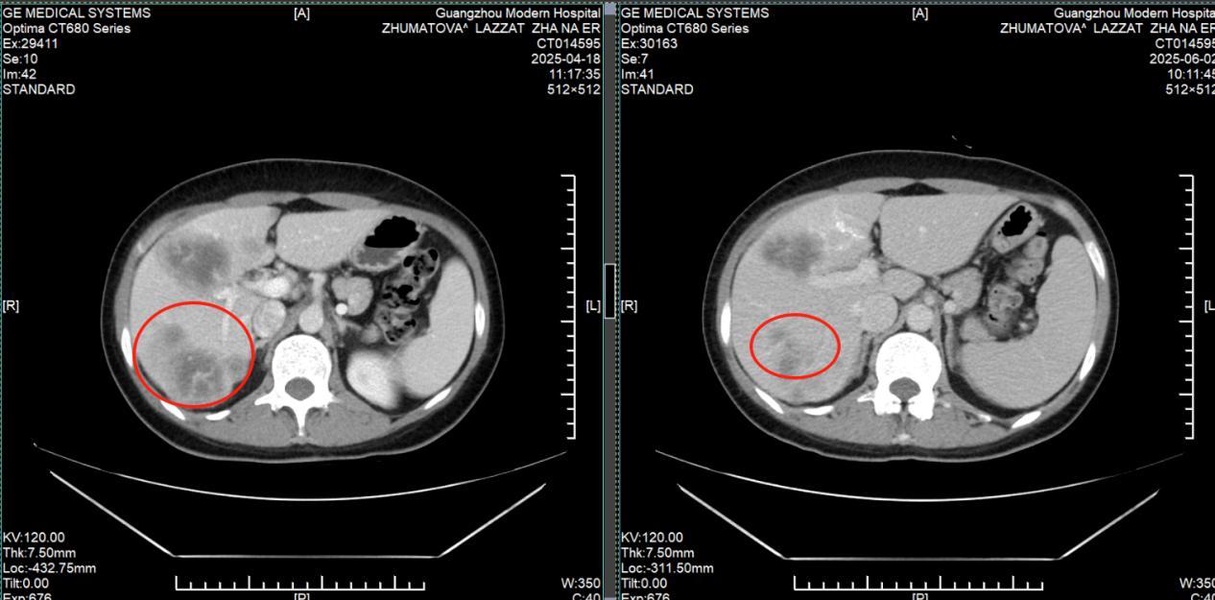

История пациента: Ляззат, 47 лет, юрист, Казахстан. Диагноз: Рак молочной железы IV стадии с множественными метастазами в печень. Тактика лечения: Комбинация интервенционной терапии (химиоэмболизация) и микроволновой абляции (МВА). Результат: Полная регрессия опухоли в молочной железе, уменьшение метастазов в печени более чем вдвое, нормализация функции печени и онкомаркеров. Неожиданная находка: когда привычный мир рухнул Ляззат - успешная женщина из Казахстана, юрист, привыкшая решать сложные задачи в суде, в начале 2025 года столкнулась с самым тяжелым делом в своей жизни. Обследование, начатое из-за усталости и скачков давления, привело к шокирующему открытию: во время УЗИ случайно обнаружили опухоль в печени, а вскоре она сама нащупала уплотнение в груди. Диагноз прозвучал как приговор: рак молочной железы IV стадии с множественными метастазами в печень. Местные врачи настаивали на единственном, по их мнению, варианте: длительном курсе химиотерапии и обязательной мастэктомии - удалении молочной железы. Принципиальное решение: сохранить не только жизнь, но и себя Для сильной и осознанной женщины это было неприемлемо. «Грудь - это не просто орган, это часть моей женской идентичности. Я никогда не соглашусь на ее удаление и должна найти лучшее решение», - так Ляззат сформулировала свою позицию. Она обратилась в клиники Турции, Индии, Южной Кореи, но нигде не получала гарантий, что лечение сможет победить рак и сохранить грудь. В момент отчаяния надежду подарила подруга, порекомендовавшая St.Stamford Modern Cancer Hospital Guangzhou и его малоинвазивные подходы.

Победа: возвращение к жизни и радости

Результат превзошел все ожидания. После двух курсов комбинированного лечения: • Опухоль в молочной железе полностью исчезла. • Метастатические очаги в печени уменьшились более чем в два раза. • Функция печени и уровень онкомаркеров (РЭА, СА153) пришли в норму. • Вернулись силы, ушла постоянная усталость. Уже в третий визит в Гуанчжоу Ляззат приехала одна, чувствуя себя настолько хорошо, что могла перенести длительный перелет и вернуться к привычной жизни. Ценить настоящее: урок, выученный с достоинством. Сегодня Ляззат не только победила болезнь, но и переосмыслила жизнь. Она благодарна команде врачей в Гуанчжоу за теплоту, поддержку и профессиональную помощь. Она активно практикует дыхательные методики и медитацию для борьбы со стрессом и участвует в жизни клиники. «Жизнь - это дар. У нас она только одна, и мы должны ее ценить, - говорит Ляззат. - Не следует переутомляться, злиться и беспокоиться. Живите настоящим и наслаждайтесь жизнью. В этом ее смысл!» Ее история - это вдохновляющий пример того, как современная медицина позволяет отстоять свое право на целостность и качество жизни даже в самой сложной ситуации.